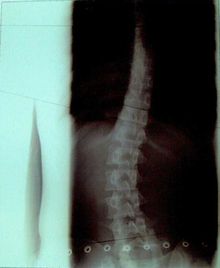

症例14)

信州大学12度→15度進行性、ここから当院通院で体操3ヶ月で6度に改善。

�@12歳 6年生 女子

平成19年6月 12度 信州大学病院 体操指導なし。

平成19年12月 15度 信州大学病院 体操指導なし。

�A平成20年1月27日 大塚整体 初診

側湾症改善大塚式鍛錬体操指導。

�B平成20年3月

6度

に改善正常範囲となる。定期検診は信州大学。

この2ヶ月間で2回体操指導。

レントゲンの比較で15度→6度の改善は明らかで脊柱がほぼ真っ直ぐです。

平成19年6月

経過観察

平成20年3月未検診

初診から体操2ヶ月後

12度

15度

6度 正常範囲